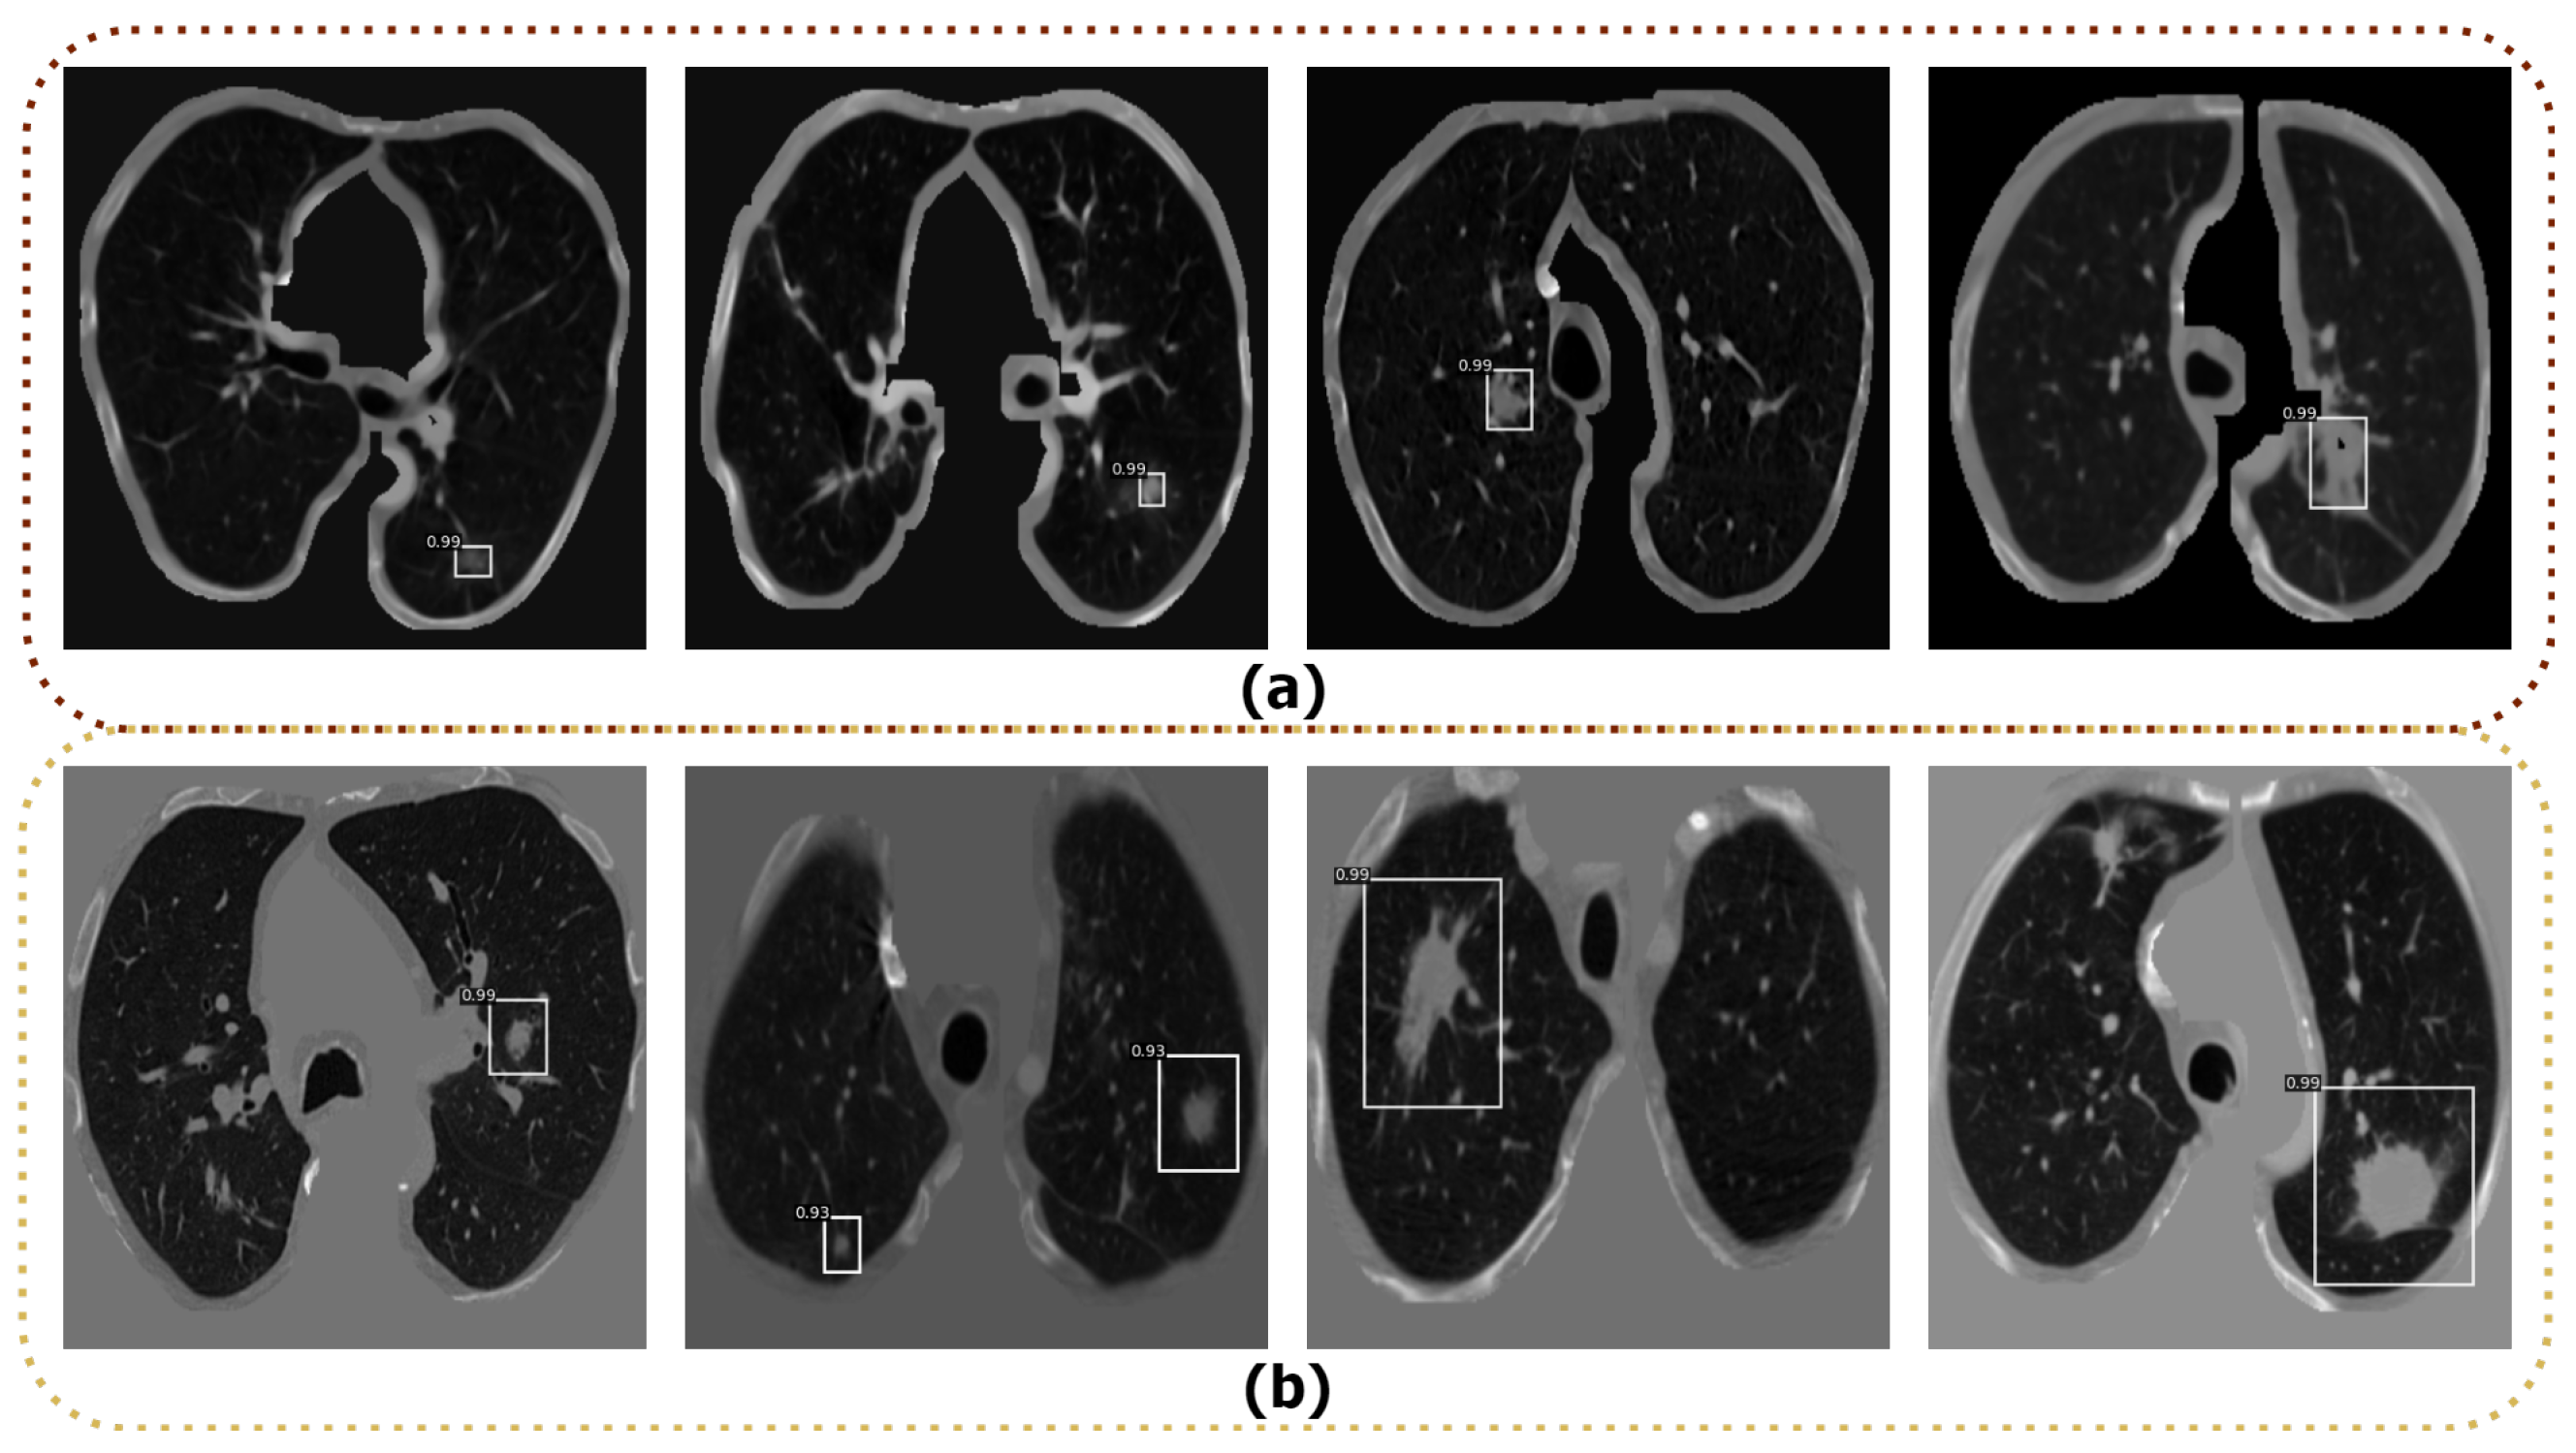

4.4. Nodule Detection